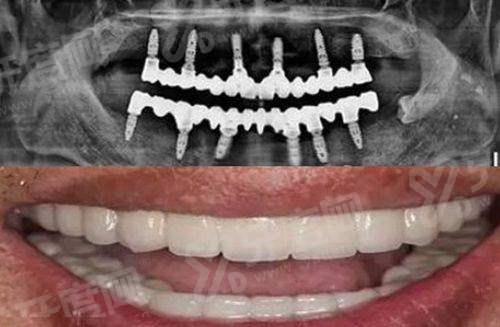

1、北京美莱口腔医院引进了数字化种植技术,通过CBCT三维立体成像,能精细获取患者口腔数据,然后制定个性化的种植方案,种植过程中使用种植导板,提高了种植的精细度和成功几率,减少了手术创伤。

3、北京美莱口腔对于牙齿修复项目,医院采用3D打印技术制作牙冠和种植体基台,不仅缩短了修复时间,还能确保修复体与口腔的贴合度,让修复后的牙齿更自然、更耐用。

北京美莱口腔半口种植牙价格:3万元起

北京美莱口腔全口种植牙价格:5万元起